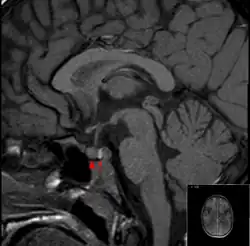

An die körperliche Untersuchung schließen sich Hormonmessungen und Funktionstests an. Bei klinischem Verdacht sollten Hormonuntersuchungen bei einem Endokrinologen vor bildgebenden Verfahren durchgeführt werden, da die bildgebenden Verfahren häufig falsch positive Befunde ergeben („Incidentalome“). Als bildgebende Verfahren finden die Röntgenaufnahme der Sella turcica im Seitbild des knöchernen Schädels, die Computertomografie, die Magnetresonanztomografie und die Somatostatin-Rezeptor-Szintigrafie Anwendung.